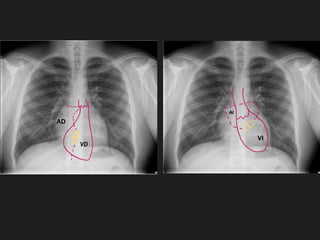

AD: Aurícula derecha

AI: Aurícula izquierda

VI: Ventrículo izquierdo

VA: Válvula aórtica

VP: Válvula pulmonar

VT: Válvula tricuspídea

VM: Válvula mitral

AD

VD

AI

VI

Tr

Mt

Ao

P

Botón aórtico

Arteria pulmonar

Art. subclavia

Vena

cava superior

cava inferior

derecha ‘interlobar’

VA

VP

VT

VM

Aorta**